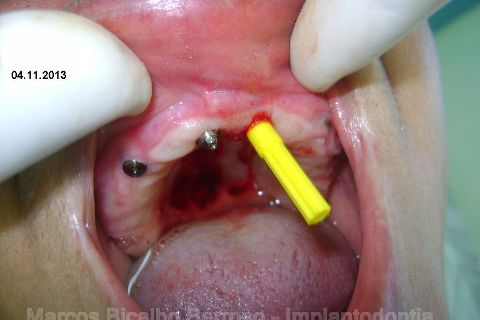

Atualização do caso clínico que já postei, "REABILITAÇÃO EM MAXILA ATRÓFICA COM IMPLANTES", um caso que inclui expansão do rebordo estreito com cinzel e martelo, expansores rosqueáveis, enxerto e instalação dos implantes distais inclinados tangenciando seio maxilar. Inclui esvaziamento do forame nasopalatino e preenchimento com biomaterial para instalação de dois implantes próximos dele. Cirurgia realizada em única sessão, com instalação dos 6 implantes. Para os colegas que não conheceram e/ou esqueceram da apresentação, este é o resumo do caso na fase cirúrgica.http://www.youtube.com/watch?v=BtvexFexRPA&hd=1

FASE PROTÉTICA DA REABILITAÇÃO EM MAXILA ATRÓFICA...incluindo a reabertura, instalação dos minipilares e PTR provisória reembasada sobre os cilindros de proteção.